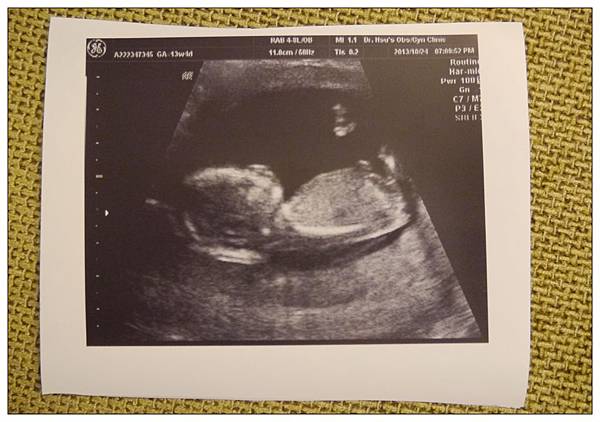

【第四次產檢】

掛號的時候護士小姐就說這次應該就可以確定性別還有正確的預產期時間了

這次蔡老爺很盡責的一直站在螢幕前拍小球~~所以關鍵時刻也拍到了~~

各~~~位~~~~觀~~~~眾

小~~~~~~~~~雞~~~~~~~~~~~雞

(等蔡小球懂事之後看到這篇不知道會不會跟為娘的翻臉XDDDD)

哈哈哈~應該有人會看得霧煞煞~反正這張就是只有拍到蔡小球的下半身就對啦~

這次蔡小球已經滿15W~身長9.13公分~體重是350g~~

嗯~~大概是一罐大瓶多多那麼重??XDD

預產期跟醫生之前算的時間差不多~就是在明年的四月底左右